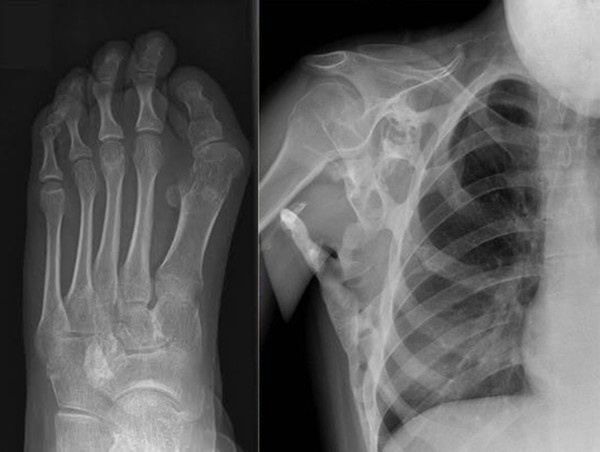

| Ảnh chụp X-quang khung xương và xương bàn chân của Seanie. |

Căn bệnh hiếm gặp này đang dần biến Seanie thành một “bức tượng sống” khi cơ, gân và dây chằng của cô gái này phát triển thành xương cứng. Điều đó có nghĩa là một bộ xương thứ hai đang “mọc” lên bộ xương cũ, tay chân cô sẽ dần cứng như một bức tượng. Hiện giờ, lưng và cổ của Seanie hoàn toàn “hóa đá”. Cô cũng không thể nâng tay lên cao quá vùng eo.